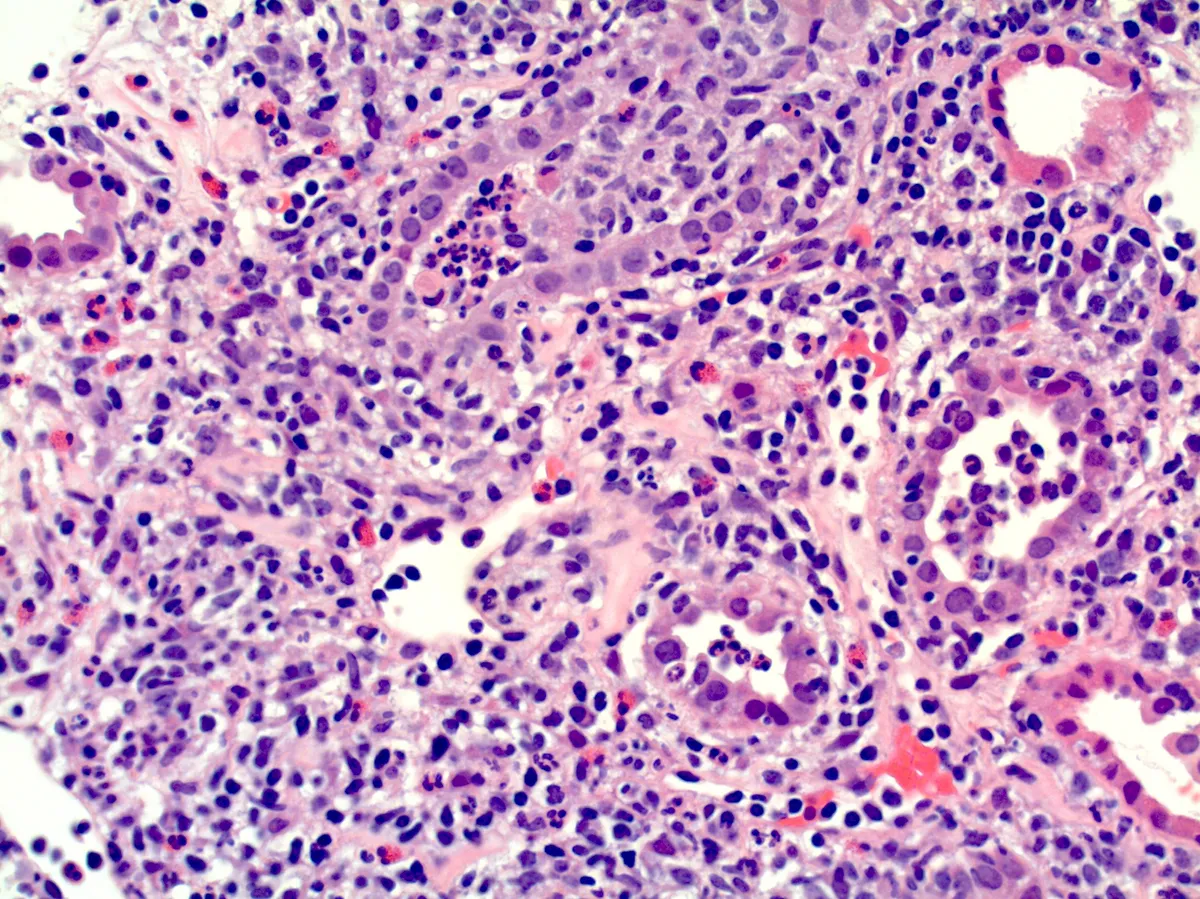

Biópsia renal: infiltrado intersticial mononuclear denso com eosinófilos e sem fibrose significativa.

3. A biópsia mostra inflamação ativa, com pouco ou nenhum grau de fibrose.

* Pacientes com fibrose intersticial extensa na biópsia

Quanto antes o corticoide for iniciado após a identificação de NIA sem fibrose (idealmente nas primeiras 2 semanas de lesão renal), maior a chance de recuperação completa da TFGe!

Se a creatinina está subindo, a droga suspeita já foi suspensa, e a biópsia mostra inflamação ativa sem fibrose... Não perca tempo! O corticoide pode evitar a evolução para DRC e até tirar o paciente da diálise!